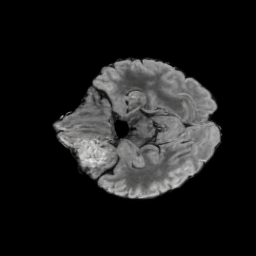

Tumour Information Preservation. For the brain tumor segmentation, we use a Swin UNETR model[27, 70], trained with random rotation, and intensity as data augmentation. In Figure 5, we highlight the tumor profiles of the generated MRIs compared to the ground truth tumour profile. In the test set with human ground-truth annotations (), the real MRI Dice score is 85.15 while the generated MRIs from a single slice have a dice score of 83.09. This shows how the generated MRIs indeed preserve the tumor information and can act as an affordable and informative pseudo-MRI, before conducting an actual costly MRI examination in hospitals.

B.4 Tumour Information Preservation

On the test set with human ground-truth annotations (), the brain volumes generated from single slice input preserve the volume of the different tumour components (paired t-test, for all 3 classes) (see Table 3). The real MRI Dice scores are put for reference to our generated MRIs. X-Diffusion outperforms baselines TPDM [36] and ScoreMRI [18] in tumour preservation (see Table 3 and Figure 12). We ran experiments comparing the tumour segmentation Dice Score varying X-Diffusion configurations. The multi-slice input X-Diffusion achieves a marginally better Dice Score than the single-slice input model (83.47 83.09). We also ran experiments with slice input used for volume reconstruction intersecting or not with tumour. We observe on average a drop of 6% Dice Score (see Table 3). Further away from the tumour the input slice for volume reconstruction is selected, and we observe a linear decrease in tumour segmentation Dice Score with the lowest value of 77.21 Dice Score (see Figure 15).